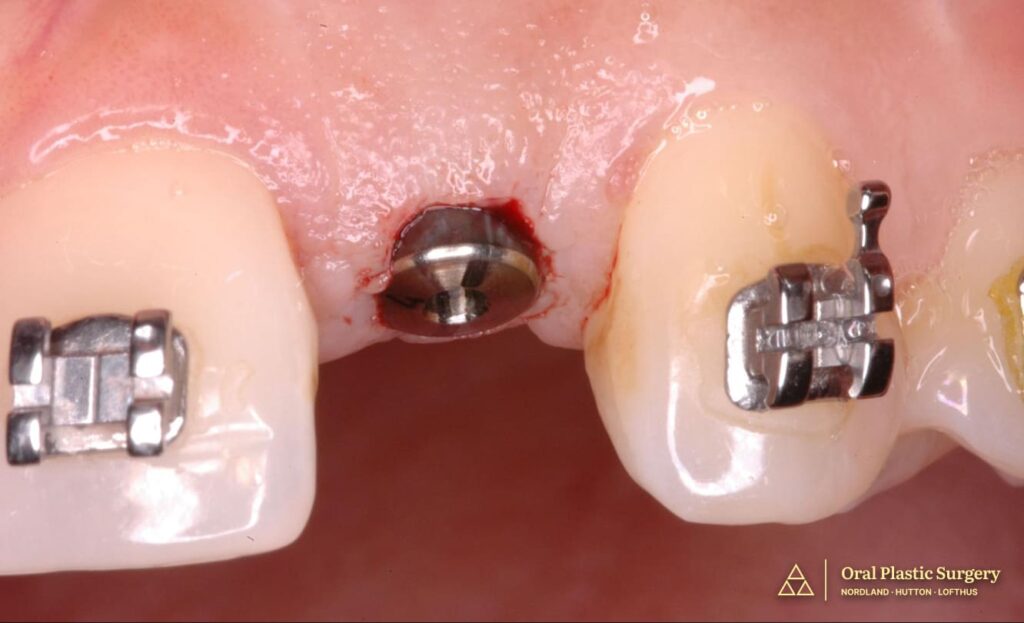

Following six months of bone block graft integration, the implant was positioned in the augmented ridge with ideal three-dimensional placement for long-term esthetic and functional success.